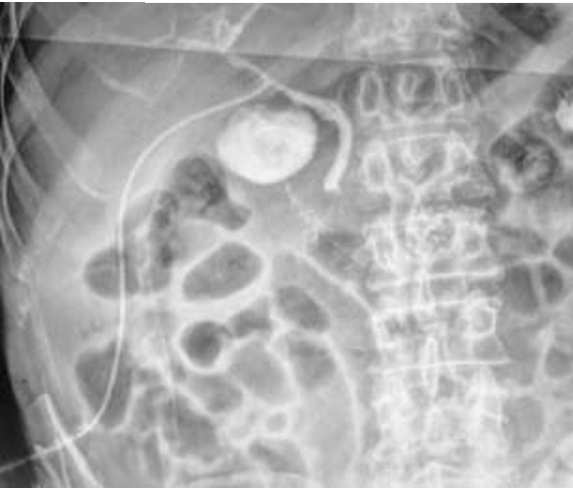

MJS. 29 anos. Submetida a procedimento cirúrgico hepatobiliar há 1 semana. Submetida à imagem complementar abaixo:

Qual exame foi realizado?